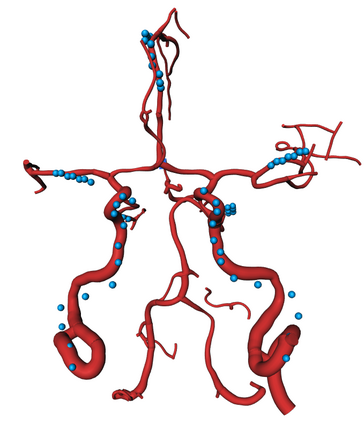

During the diagnosis of ischemic strokes, the Circle of Willis and its surrounding vessels are the arteries of interest. Their visualization in case of an acute stroke is often enabled by Computed Tomography Angiography (CTA). Still, the identification and analysis of the cerebral arteries remain time consuming in such scans due to a large number of peripheral vessels which may disturb the visual impression. In previous work we proposed VirtualDSA++, an algorithm designed to segment and label the cerebrovascular tree on CTA scans. Especially with stroke patients, labeling is a delicate procedure, as in the worst case whole hemispheres may not be present due to impeded perfusion. Hence, we extended the labeling mechanism for the cerebral arteries to identify occluded vessels. In the work at hand, we place the algorithm in a clinical context by evaluating the labeling and occlusion detection on stroke patients, where we have achieved labeling sensitivities comparable to other works between 92\,\% and 95\,\%. To the best of our knowledge, ours is the first work to address labeling and occlusion detection at once, whereby a sensitivity of 67\,\% and a specificity of 81\,\% were obtained for the latter. VirtualDSA++ also automatically segments and models the intracranial system, which we further used in a deep learning driven follow up work. We present the generic concept of iterative systematic search for pathways on all nodes of said model, which enables new interactive features. Exemplary, we derive in detail, firstly, the interactive planning of vascular interventions like the mechanical thrombectomy and secondly, the interactive suppression of vessel structures that are not of interest in diagnosing strokes (like veins). We discuss both features as well as further possibilities emerging from the proposed concept.